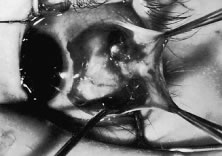

A Stevens' tenotomy hook is passed by the surgeon into the incision and is rotated so that it can be slid underneath the muscle insertion with the tip of the hook held tangential to the globe (Fig. 12). The hook should be passed 2 to 3 mm posterior to the expected location of the muscle insertion. Care is taken not to incorporate intramuscular septum or other adventitial tissue on the hook. When the lateral rectus muscle is secured with the Stevens' or Jameson muscle hook, care should be taken not to bring the inferior oblique muscle up to the insertion (Fig. 13). When the muscle is secured with the Stevens' hook, the hook and the inferior edge of the muscle insertion are elevated and a Jameson muscle hook is passed between the tented muscle tissue and the sclera to secure the muscle at its insertion (Fig. 14). Care is taken to include the entire insertion of the tendon on the hook. The tip of the Jameson hook is gently elevated by depressing the heel of the hook. This maneuver helps to ensure that the entire tendon of the muscle remains captured on the hook. A Stevens' tenotomy hook is placed in the incision, this time anterior to the insertion beneath the conjunctiva (Fig. 15). The Stevens' hook is passed posterior over the orbital surface of the muscle (Fig. 16). Gentle pressure on the Stevens' hook is directed posterior so that the check ligaments and Tenon's tissue that overlie the muscle belly are separated from the muscle capsule with blunt dissection. The hook usually is passed posterior for about 10 mm. When recessing a lateral rectus, attachments between the underside of the lateral rectus and inferior oblique are broken (Fig. 17). Two or three passes over the muscle are made, and, with simultaneous countertraction on the Stevens' hook and the Jameson hook, the conjunctiva is elevated and pulled over the tip of the Jameson hook (Fig. 18A and B).

Fig. 12. The incision is held open with a Manhattan forceps. A Stevens' tenotomy hook is introduced into the incision. The hook is being placed under the rectus muscle without dragging Tenon's tissue and intermuscular septum into the insertion.

Fig. 13. When approaching the lateral rectus, the inferior oblique muscle can be brought up to the lateral rectus insertion. In this instance, the tendon of the lateral rectus muscle should be separated from the inferior oblique muscle with blunt dissection and repositioned back into the incision.

Fig. 14. A Jameson hook is used to spread the incision open with countertraction against the Stevens' hook, which is under the rectus muscle. Then, the Stevens' hook elevates the conjunctiva and the muscle insertion. The Jameson muscle hook is inserted underneath the Stevens' hook to secure the entire insertion of the tendon of the rectus muscle.

Fig. 15. The Jameson hook has been placed under the rectus insertion. A Stevens' tenotomy hook is introduced anterior to the muscle insertion, and with an anterior-posterior movement, the conjunctiva is bluntly dissected free from the anterior extension of the rectus muscle. The Stevens' hook is moved anterior underneath the conjunctiva to approximately 3 or 4 mm anterior to the rectus muscle insertion. It is then passed over the insertion and directed posterior, following a path similar to the course of the muscle from its origin. The hook is carefully passed posterior for about 8 to 10 mm to separate adhesions between the muscle capsule and the overlying Tenon's tissue.

Fig. 16. Countertraction between the Stevens' hook and the Jameson hook will open the incision over the muscle insertion, exposing the muscle tendon on the Jameson hook. The intermuscular septum and anterior Tenon's capsule remain at the upper pole of the insertion. Exposure is provided by a Stevens' tenotomy hook.

Fig. 17. When recessing a lateral rectus, a Jameson hook is passed posterior on the orbital portion of the lateral rectus to breach attachments between the inferior oblique and the lateral rectus.

Fig. 18. A. The muscle tendon is placed on the Jameson hook, and the superior pole of the muscle insertion is exposed with the Stevens' muscle hook. B. View to show the position of the surgeon's hands (right and left) and the assistant's hands on the Jameson (superior) and Stevens' hooks (inferior).

The intermuscular septum and Tenon's capsule at the ball-like tip of the Jameson hook are incised with a Westcott scissors (Fig. 19). A Manhattan forceps can be used to elevate the intramuscular and Tenon's tissue to facilitate this step. Care is taken to incorporate the entire muscle tendon on the Jameson hook before this cut is made. If it is evident that there is residual tendon that is not placed on the hook, the additional tendon, intramuscular septum, and anterior Tenon's tissue are reflected over the tip of the Jameson hook with the closed tips of the Westcott scissors or a small muscle hook.

Fig. 19. A. The intermuscular septum is grasped with a Manhattan forceps. B. A Westcott scissors is used to cut open the intermuscular septum and expose the superior pole of the rectus muscle insertion. The scissors are removed after the placement of a Stevens' hook in the opening that has been created in the intermuscular septum.

A Stevens' hook is inserted in the opening in the intermuscular septum created by the scissors and is passed anterior to the insertion. Parks has referred to this maneuver as the “pole test.” This maneuver is done to verify that the tendon of the muscle has not been split and that the complete muscle tendon is incorporated on the hook. Leaving residual slips of muscle tendon will partially or completely negate the effect of a recession procedure (Fig. 20A and B).

Fig. 20. A. After the Stevens' hook is inserted into the incision created by the Westcott scissors, the hook is moved anteriorly to pass over the upper pole of the insertion of the rectus muscle. If the hook cannot pass anterior to the rectus muscle, the insertion may have been split by the Jameson hook. Fibers of the rectus muscle tendon that are not on the hook will remain at the insertion. It is important to include these fibers to achieve a reproducible recession effect. B. Residual tendon fibers of a detached lateral rectus. These are demonstrated with the Steven's muscle hook.